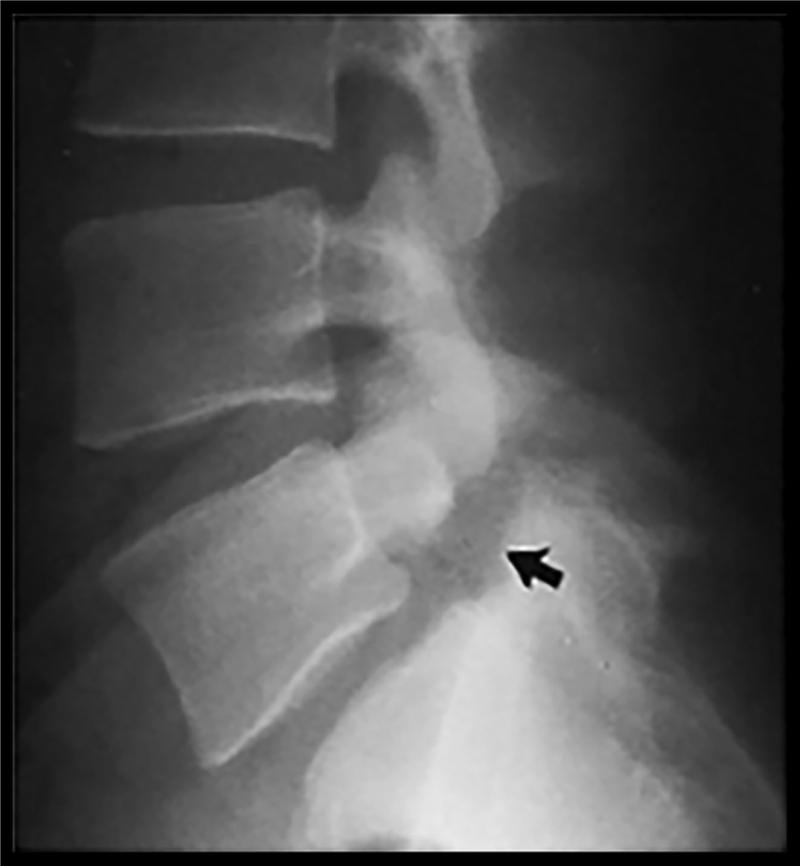

Hẹp ống sống thắt lưng với hẹp ống sống trung tâm và ngách bên có thể xảy ra trong bối cảnh thoái hóa cột sống đơn thuần hoặc có thể do trượt đốt sống gây ra, trượt đốt sống là tình trạng đốt sống phía trên trượt ra trước so với đốt sống phía dưới. Meyerding dựa vào tỷ lệ % của phần trượt ra trước của đốt sống phía trên so với đốt sống phía dưới để xếp mức độ trượt (hình 4):

Độ I: ≤25%, độ II: 26-50%, độ III: 51-75%, độ IV: 76-100%

Hình 4. Phân độ trượt theo Meyerding cải tiến

Trượt đốt sống ra trước được chia độ theo phân loại Meyerding: Độ I: ≤25%, độ II: 26-50%, độ III: 51-75%, độ IV: 76-100%. Đánh giá hình ảnh học trượt đốt sống mức độ không chỉ giới hạn ở việc đánh giá mức độ trượt, mà các bằng chứng khoa học gần đây cho thấy đo góc gù (angular kyphotic deformity) tại vị trí thắt lưng cùng có vai trò quan trọng hơn mức độ trượt trong tiên lượng nguy cơ trượt tiến triển. Một số hệ thống phân loại mới kết hợp đánh giá mức độ trượt và các thông số về góc tại vị trí trượt để mô tả trượt đốt sống mức độ cao và cung cấp thông tin để lên kế hoạch phẫu thuật.

Trượt đốt sống thắt lưng (TĐSTL) được chẩn đoán thường quy bằng Xquang (hình 13) và/hoặc CT. Ở thể tiêu eo, có thể thấy hình ảnh kinh điển “Scottie dog”, là chỉ dấu tiêu eo.

Hình 13. Trượt đốt sống do tiêu eo